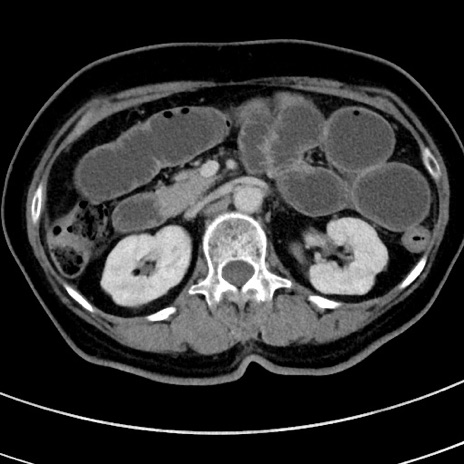

症例9(横断像)

冠状断像

【症例】 60歳代女性

【主訴】むかつき、みぞおちの痛み

【現病歴】3日前よりむかつきがあり、食事がとれない。

【既往歴】糖尿病

【身体所見】発熱なし、心窩部圧痛軽度あるも、腹膜刺激症状なし。

【データ】WBC 7400、CRP 1.92